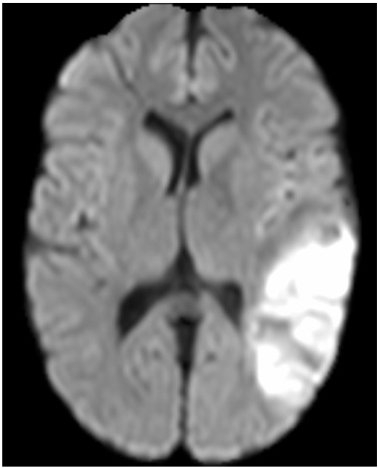

Parallel Capsule Net for Ischemic Stroke Segmentation

MD Sharique, Uday Bondi Pundarikaksha, Pradeeba Sridar, R S Ramakrishnan, R Krishnakumar

Pre-print on bioRxiv

A novel neural network architecture, Parallel Capsule Net (PCN) for segmentation of Ischemic Stroke.